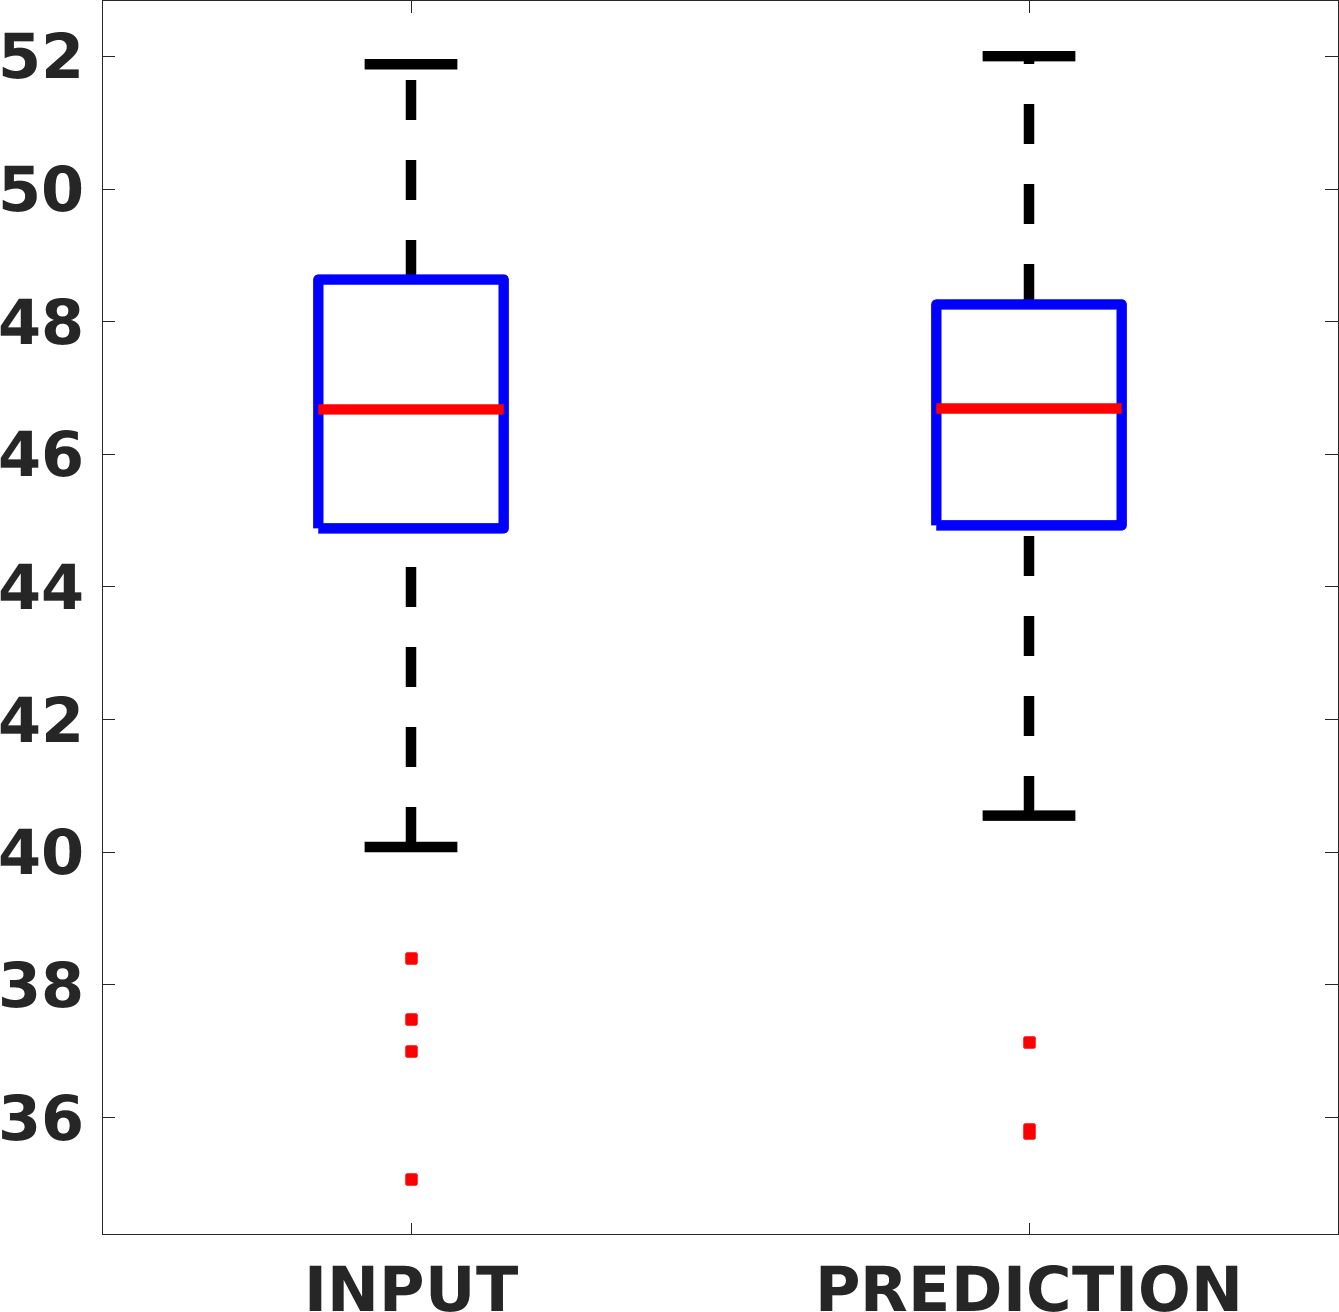

Fig. 7(a-b-c, left) shows the box plot of the statistics of the PSNR on three different anatomical districts, comparing the target images with the prediction and the cubic convolution, respectively. The metrics are computed on a data set of 200 images of the same district and with the same up-sampling factor. We report that the PSNR median value improves of on obstetric 2X raw images, on cardiac 2X raw images, and on abdominal raw 4X images.

Fig. 8 shows the box plot of the SSIM (a-b-c, left) and MAE (a-b-c, right) quantitative metrics, as performed for PSNR metric. Also, these metrics show that our method improves the results of Cubic convolution both in terms of average value and variability. For example, the SSIM median value improves of on obstetric 4X images and the MAE median value improves of on cardiac 2X images.

Fig. 17 (left) shows the box plot of the quantitative metrics, comparing the target images with the prediction and the Cubic convolution, respectively. The PSNR metric is computed on a data set of 200 images, belonging to the same district, and with the same up-sampling factor. Analysing the obstetric anatomical district and concerning the corresponding raw images (Fig. 7 (a, left)), the denoising allows the network to significantly improve the results of the up-sampling and the prediction. In particular, comparing the target images with the predicted images, the median PSNR value of obstetric 2X denoised images is 51.8, compared to the median PSNR value of obstetric 2X raw images which is 36.9.